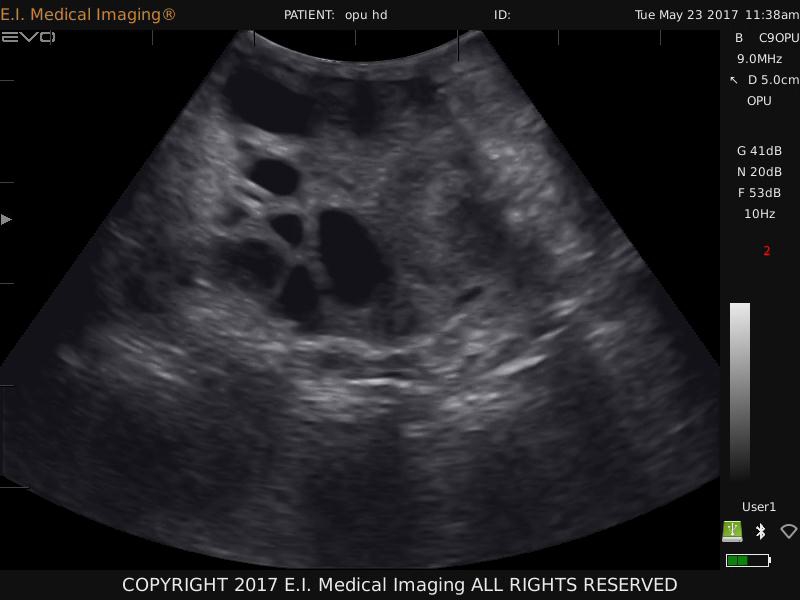

在使用牛用活体采卵仪进行实时监测时,技术人员应重点关注直径在 2mm以上 的卵泡。实验证明,3mm至8mm 是**的采卵范围。处于这一区间的卵泡,其内部的卵母细胞发育状态相对稳定,体外成熟培养(IVM)的成功率更高,具有更强的后续发育潜力。

因此,借助牛用活体采卵仪的超声引导功能,对卵泡群进行精准筛选,是避开低质卵泡、捕捉优质细胞的关键。

精准定位:配合兽用B超设备,设备能够清晰呈现卵巢上的卵泡分布,帮助操作者精准锁定3mm-8mm的目标卵泡。